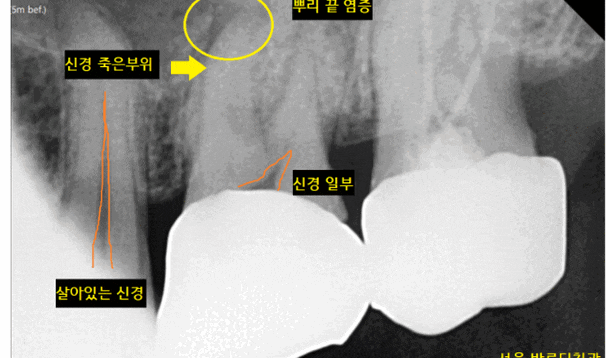

x-ray를 통해 검사부터 해보았는데요.

치아 뿌리에 염증이 있는 치아가 많았습니다.

불편을 호소하시는

왼쪽 위에 치아를 검사해보았습니다.

이런 이런..

신경이 죽었네요.

신경이 살아있으면

검정색 선이 보이는데요.

환자분은 신경이 안보였습니다.

신경이 이미 괴사

죽어버려서 검정색 선이 없어졌네요~~

비가역적 치수염으로 진단되었습니다.

뜻을 풀어보자면

되돌아올 수없는 신경 염증이라는 뜻입니다.

회복 불가능!!

신경이 죽은 치아 뿌리 끝에 염증이 보이고

상악동까지 염증이 번져서 눈 두덩이가 아픈거라

치료가 필요했습니다.